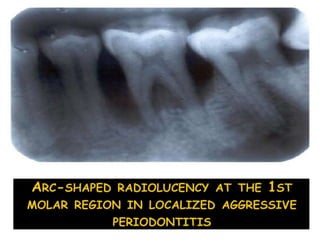

Classic diagnostic sign:

Vertical loss of alveolar bone around 1st

molars & incisors

Beginning around puberty in an otherwise

healthy teenagers

―Arc shaped loss of alveolar bone

extending from distal surface of 2nd

premolar to mesial surface of second

molar‖

Classic diagnostic sign: Verticalloss of alveolar bone around 1st molars & incisors Beginning around puberty in an otherwise healthy teenagers ―Arc shaped loss of alveolar bone extending from distal surface of 2nd premolar to mesial surface of second molar‖